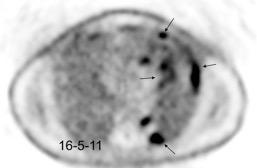

Carcinoma de mama con derrame pleural e implantes metastáticos

Makis W et al. Spectrum of Malignant Pleural and Pericardial Disease on FDG PET/CT. AJR. 2012